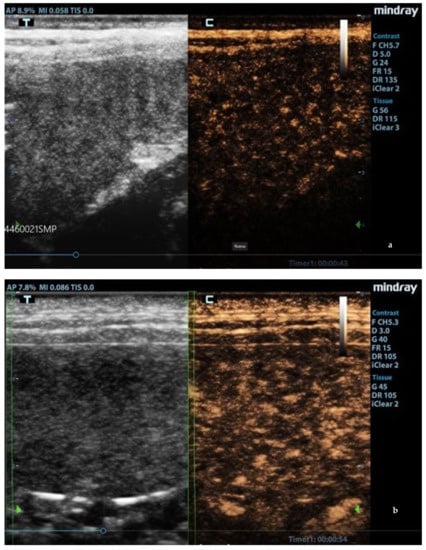

In leishmaniotic dogs without splenic changes detectable from ultrasound examination and control dogs, CEUS exams showed the normal rapid enhancement of splenic arteries (10–13 s) and a heterogeneous phase of the enhancement of splenic tissue that became homogeneous at the end of wash-in with a slow decay (Figure 3).

Figure 3.

Normal spleen images acquired during CEUS (contrast-enhanced ultrasonography) exam. (a) Enhancement of the splenic arteries at 8 s after contrast injection; (b) beginning of heterogeneous phase of enhancement 10 s after contrast injection; (c) homogeneous enhancement at 60 s after contrast injection. F: probe’s frequencies; D: distance; G: gain; FR: frame rate; DR: dynamic range; AP: acoustic power; MI: mechanichal index; TIS: tissue imaging specific; M9: ultrasound system; T: tissue; C: contrast. Green arrows: focal points.

Enhancement in the moth-eaten parenchymas had a heterogeneous distribution pattern with hypoenhancement/no enhancement areas in both the wash-in and wash-out phases; in marbled spleens, enhancement intensity was weak and heterogeneous (Figure 4 and Figure 5).